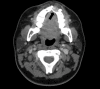

The diagnosis of craniofacial osteosarcoma can be quite challenging, and the condition often goes unrecognized for a considerable period of time. In this report, we discuss the case of a 21-year old woman who presented with a one-year history of a small swelling over the left maxillary alveolar ridge. Upon further investigation, the histopathological examination showed high-grade chondroblastic osteosarcoma. The option of four cycles of neoadjuvant chemotherapy regimen preoperatively was chosen, and left inferior maxillectomy was performed along with reconstruction with obturator prosthesis. This case highlights the difficulties encountered in such rare cases of craniofacial osteosarcomas both in terms of the delay in the establishment of the diagnosis as well as management protocol. A high index of suspicion is required in cases of craniofacial osteosarcoma and early surgical resection with adequate safety margins is warranted.